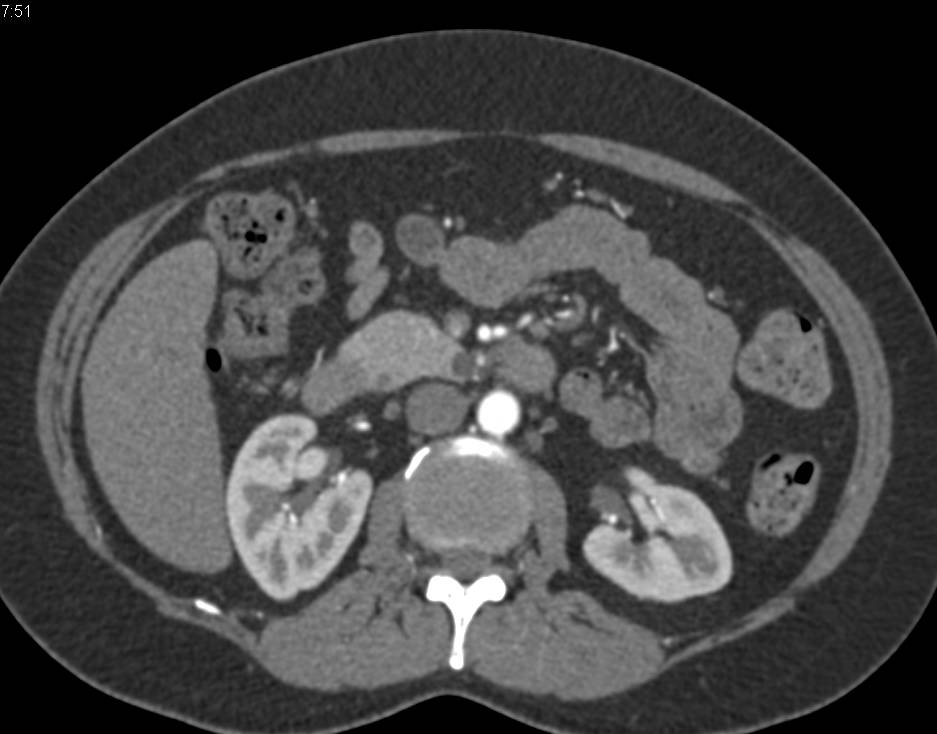

Neuroendocrine Tumor of the Head of the Pancreas